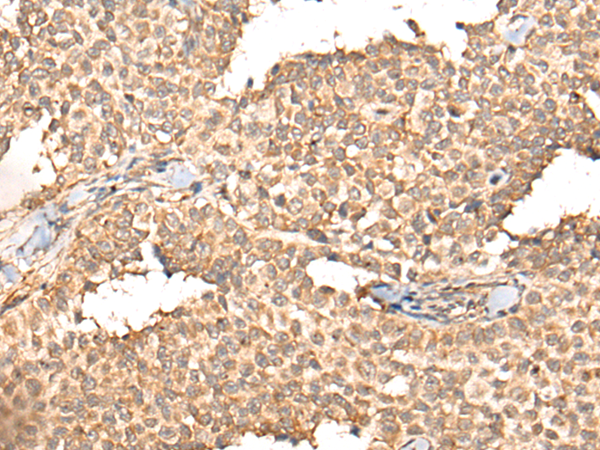

IHC positive control: |

Human liver cancer and human ovarian cancer |

ELISA, IHC |